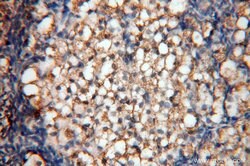

SYK Rabbit anti-Human, Mouse, Rat, Polyclonal, Proteintech

This gene encodes a member of the family of non-receptor type Tyr protein kinases. This protein is widely expressed in hematopoietic cells and is involved in coupling activated immunoreceptors to downstream signaling events that mediate diverse cellular responses, including proliferation, differentiation, and phagocytosis. It is thought to be a modulator of epithelial cell growth and a potential tumor suppressor in human breast carcinomas. Alternatively spliced transcript variants encoding different isoforms have been found for this gene.Specifications

| Immunohistochemistry (Paraffin) | |